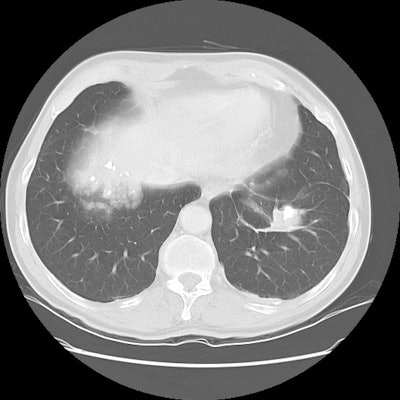

The patient shown on the CT images below presented for evaluation of an enlarging abnormality on CXR. The CT demonstrates exuberant pleural plaque disease along the right diaphragmatic surface. There is a soft tissue mass within the left lower lung that contains a large eccentric calcification. Lung markings radiate into this lesion from the adjacent lung parenchyma and there is distortion of the major fissure. The finding suggested rounded atelectasis, however, the lesion had more aggressive features more inferiorly (see lower CT images). PET images are shown below CT's.